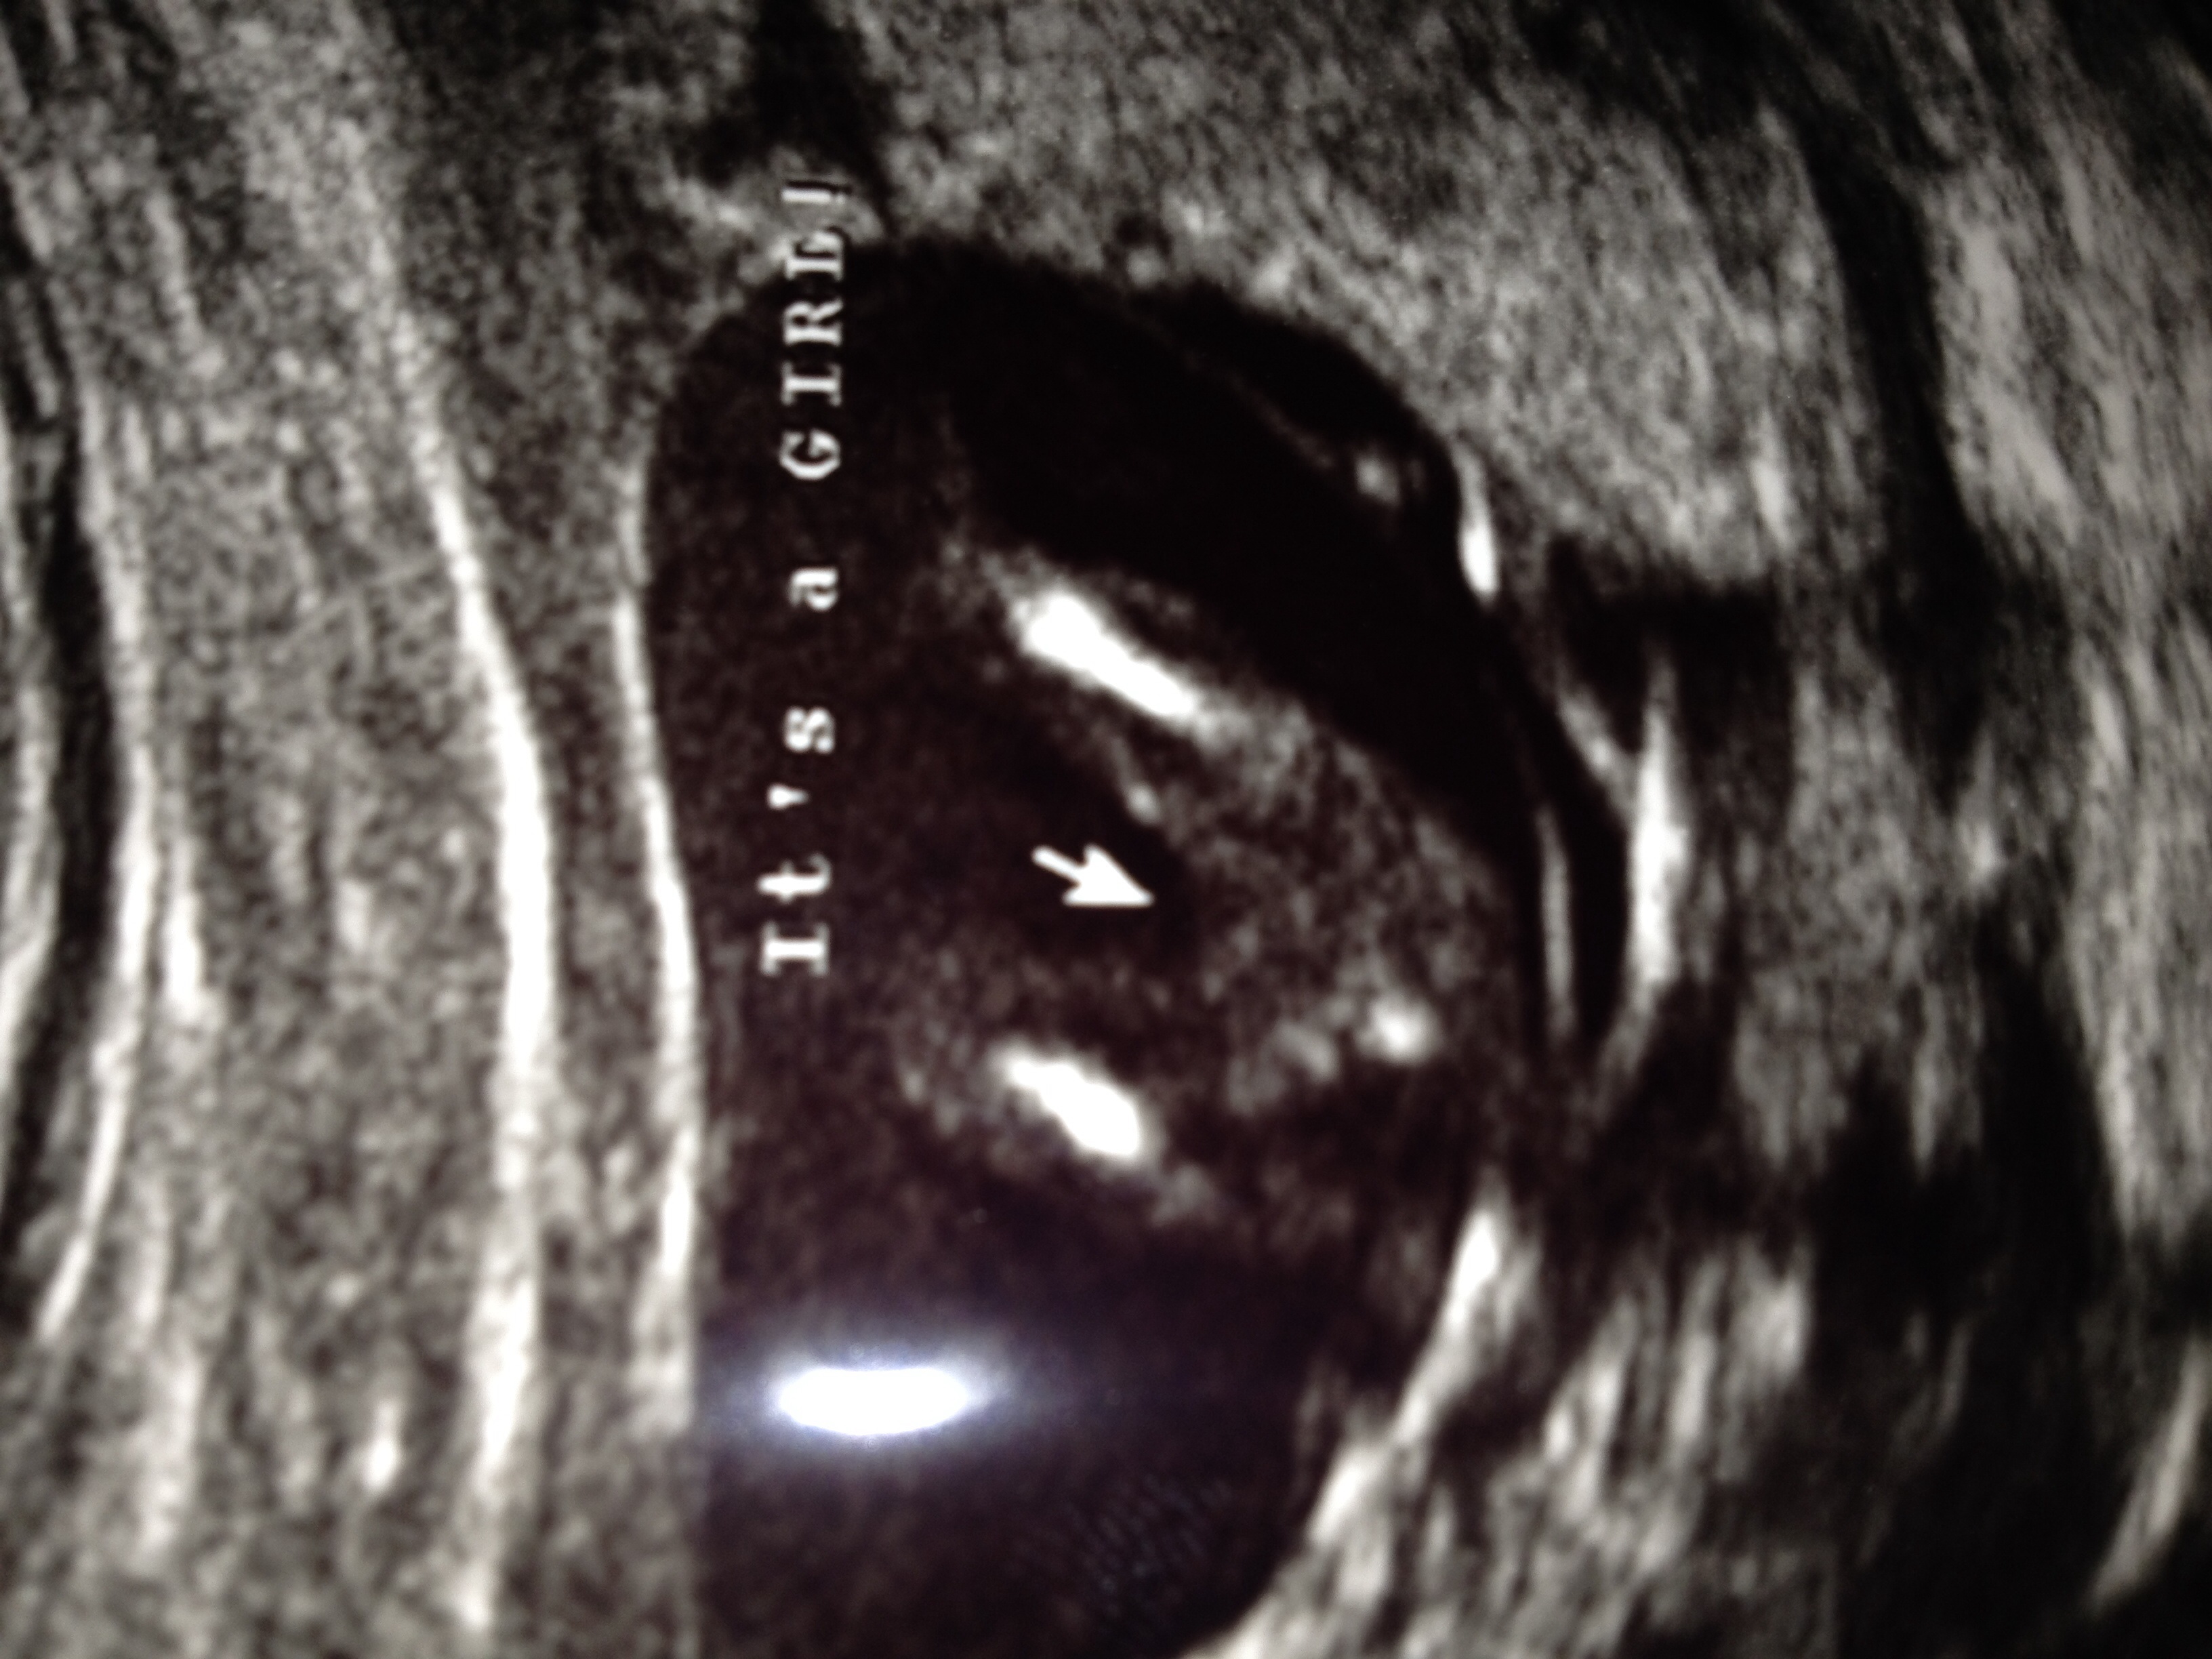

So happy to announce we have a confirmed GIRL! Baby Piper Elizabeth! Thank you to everyone who guessed on our nub shot. All of our dreams have been answered and I am truly blessed!

Attachment 24822